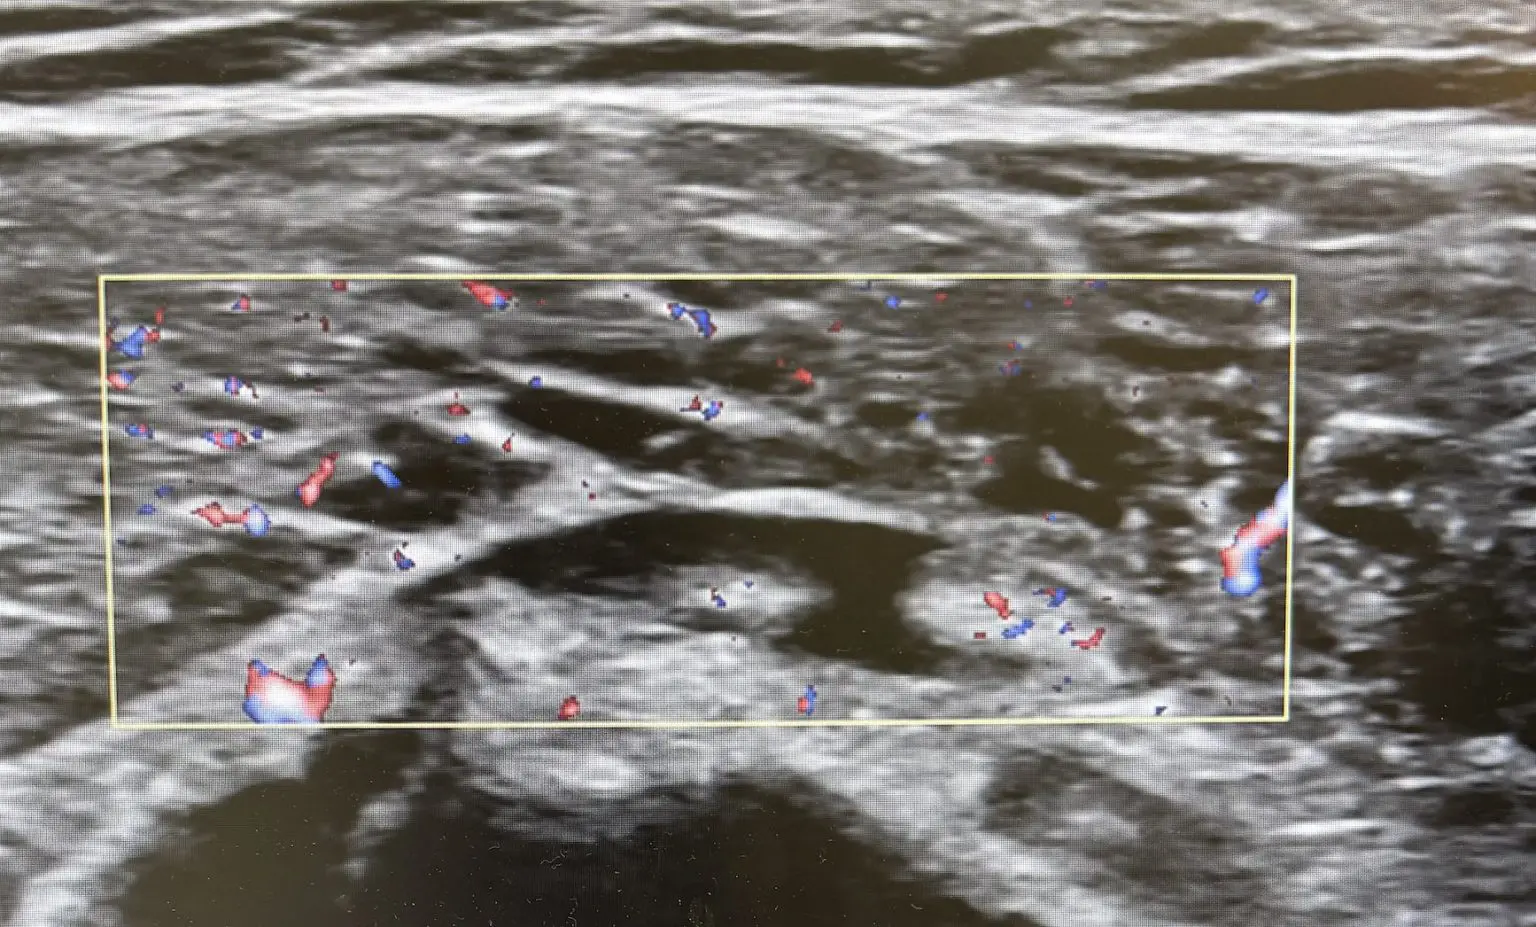

- 炎症や腫れに カラードプラ

たとえば「腕を横に挙げるとズキッと痛む」というとき、その動作を再現しながらエコーを当てると、どの筋肉がひっかかっているのか、どの部位に炎症があるのかをリアルタイムに確認できます。

さらに、診察室で患者さんと一緒に画面を見ながら説明できるのも大きなメリットです。白黒の映像ではありますが、実際に「ここが腫れている部分ですよ」と示されると、患者さん自身も納得感を持って治療に取り組むことができます。